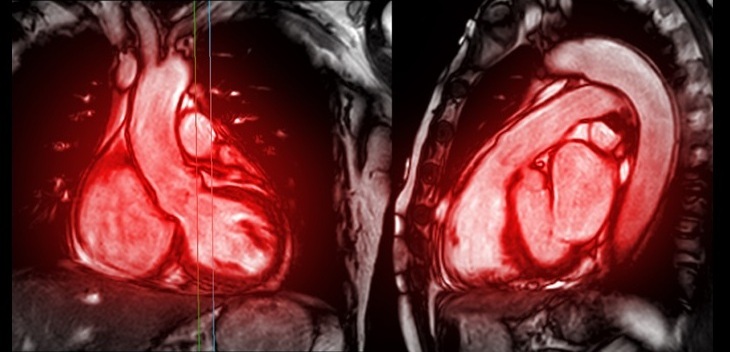

- New MRI Technique Reveals Hidden Heart Issues

- MRI Scans Can Identify Cardiovascular Disease Ten Years in Advance